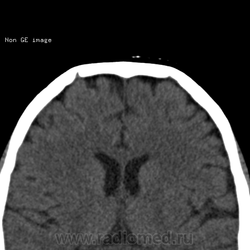

Нейрохирург принес на консультацию снимки. Пациенту был выставлен диагноз в частном диагностическом центре эозинофильная(-ные) гранулёмы лобных костей. Как вам?

А, не совпадают ли эти "гранулёмы" топографически с венозными выпускниками?

какие-то дырки в лобных костях

Пахионовы ямки. Валентин Львович, Вы первый.

Согласна, конечно пахионовые грануляции.

Конечно же это не эозинофильные гранулёмы, пациента прислали к нейрохирургу, предварительно расстроив.

Вижу эти образования как ямочки грануляций, сообщающиеся с диплоетическими венами

Пахионовы грануляции, конечно! Еще они иногда вдаются в просвет венозных синусов, и тогда рентгенологи пишут "тромбоз")